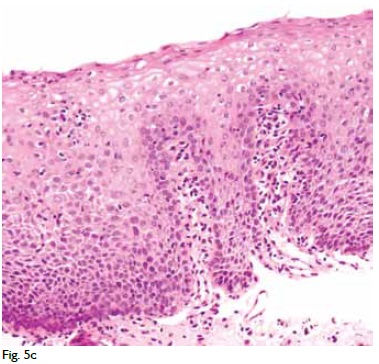

LG: Esta é a 1ª ressonância do doente e vamos agora ver a 2ª: nota-se que os trajectos fistulosos são exactamente os mesmos. Há ainda a fístula transfinctérica com derivação para a esquerda, trajecto fistuloso de grandes dimensões para a fossa ísquio-anal direita e um trajecto na nádega direita que acaba por drenar na pele em dois sítios. Os trajectos fistulosos são os mesmos mas há uma diferença entre as duas que tem a ver com o maior brilho, ou seja, é mais branco, isto é, há aumento do hipersinal em T2, o que tem tradução fisiopatológica: significa maior grau de inflamação (Fig. 5). Havia, pois, agravamento dos achados perianais, apesar dos aspectos fistulosos serem os mesmos.